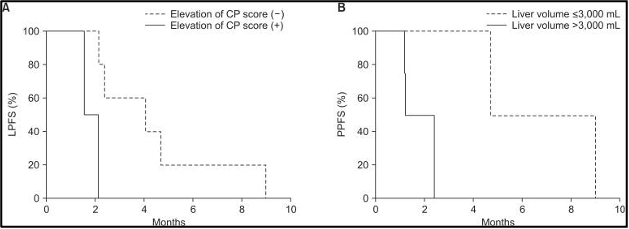

לאחר 3 חודשים, ההישרדות ללא התקדמות מקומית (LPFS) הייתה 30% וההישרדות ללא התקדמות כאב (PPFS) הייתה 58.3%. גורמים פרוגנוסטיים אפשריים הקשורים לשיעורי ההישרדות נמצאים בטבלה 3. עלייה בדירוג צ'יילד-פו (Child-Pugh score) (p = 0.04) (איור 5A) בחודש אחד לאחר טיפול קרינתי לכל הכבד (WLI) עם היפרתרמיה היה גורם פרוגנוסטי משמעותי להישרדות ללא התקדמות מקומית (LPFS). הישרדות ללא התקדמות מקומית (LPFS) נוטה להיות גבוהה יותר במטופלים ללא גרורות חוץ-כבדיות משולבות (combined extrahepatic metastasis) (p = 0.1) (איור משלים 1).

להלן איור 5: עקומות ההישרדות של קפלן-מאיר בהתאם לגורמים פרוגנוסטיים מובהקים. (A) עלייה בדירוג צ'יילד-פו (CP) בחודש אחד על ההישרדות ללא התקדמות מקומית (LPFS), (B) נפח כבד שלם (Whole liver volume) גדול מ-3,000 מ"ל המייצג נפח גידול גרורתי על ההישרדות ללא התקדמות כאב (PPFS)

נפח כבד שלם (Whole liver volume) גדול מ-3,000 מ"ל (p = 0.02) (איור 5B), אשר ייצג בעקיפין נפח גידול גרורתי (metastatic tumor volume), היה קשור באופן מובהק להישרדות ללא התקדמות כאב (PPFS) נמוכה יותר. הישרדות ללא התקדמות כאב (PPFS) נוטה להיות גבוהה יותר במטופלים עם קרצינומה נוירואנדוקרינית (neuroendocrine carcinoma) (p = 0.11) (איור משלים 2) ורמה ראשונית של אנטיגן קרצינואמבריוני (CEA) גבוהה מ-50 ננוגרם/מ"ל (p = 0.12) (איור משלים 3). תגובה אובייקטיבית (Objective response) לאחר חודש אחד לא הייתה קשורה להישרדות ללא התקדמות כאב (PPFS) (p =0.43).

למרות שאיכות חיים הקשורה לבריאות (HRQoL) הוערכה בפחות ממחצית מהמטופלים 2-3 חודשים לאחר הטיפול, איכות החיים הקשורה לבריאות (HRQoL) נשמרה במטופלים שהוערכו. בדומה לאיכות חיים הקשורה לבריאות (HRQoL), התקדמות הכאב בהתאם לקריטריונים של IBMCG התעכבה עד לחציון של 4.7 חודשים. בנוסף, התקדמות הסימפטומים הייתה קשורה בבירור לנפח הכבד כולו (whole liver volume) המייצג את עומס הגידולי הגרורתי (metastatic tumor burden). לא נצפתה התקדמות כאב במטופלים עם נפח הכבד כולו (whole liver volume) של פחות מ-3,000 מ"ל במהלך המעקב.